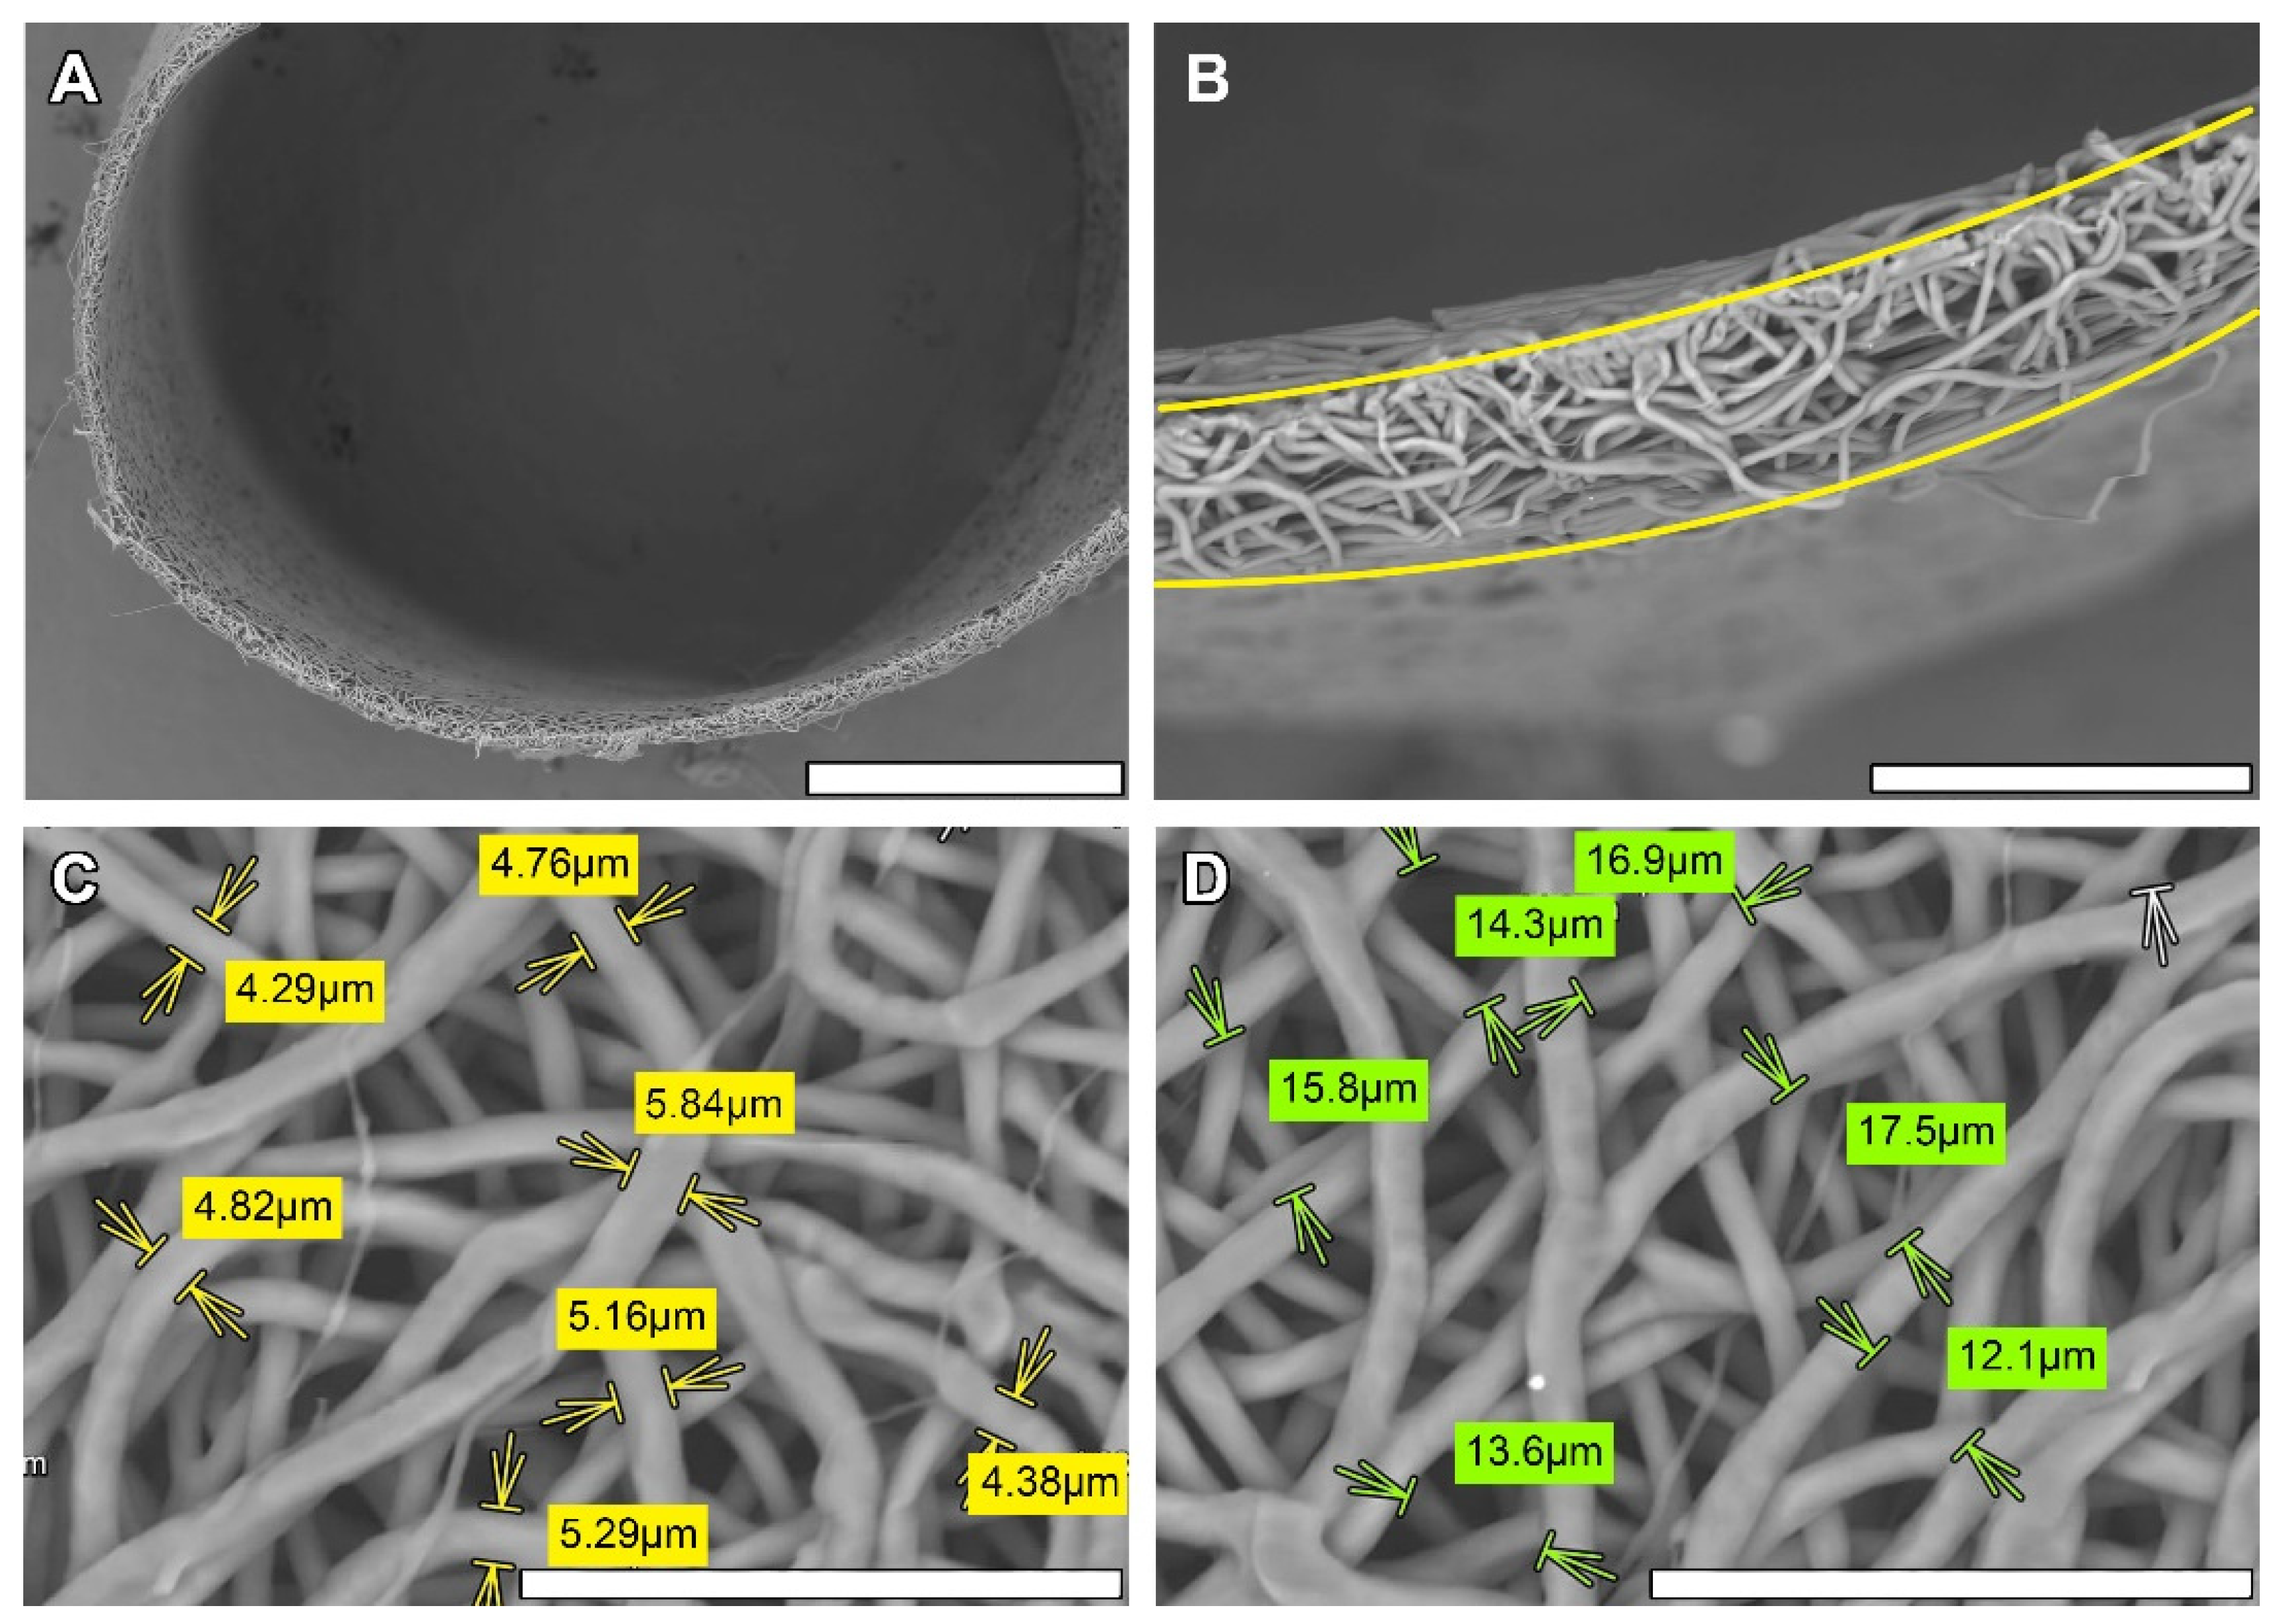

2.3. Scanning Electronic Microscopy (SEM)

3.1. Non-Implanted Scaffolds